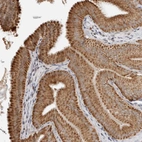

Immunohistochemical staining of human gallbladder shows cytoplasmic positivity in glandular cells.